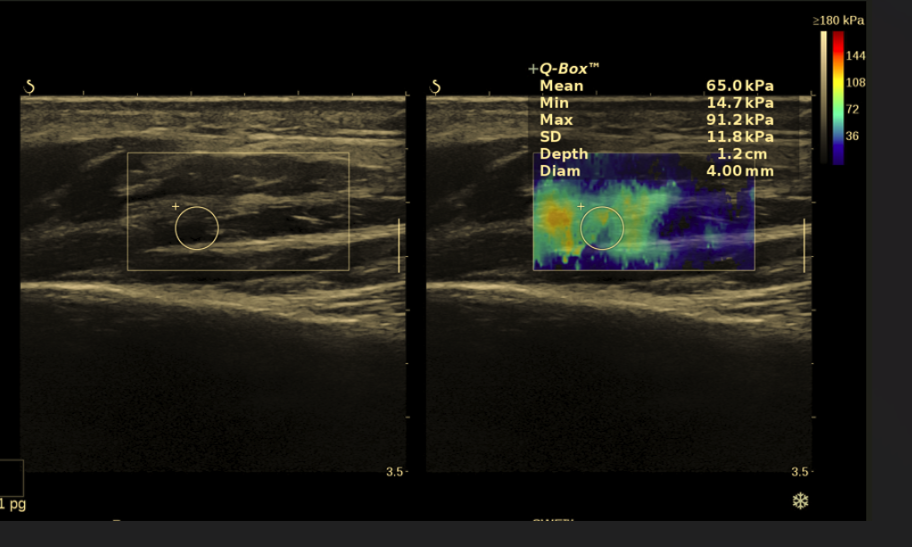

4. Nerw błędny – czy USG może go ocenić przy tinnitus?

Nerw błędny nie jest głównym nerwem słuchowym, ale poprzez regulację autonomiczną może pośrednio wpływać na odczuwanie szumów.

Czy USG wykryje zaburzenia nerwu błędnego?

W USG szyi można ocenić:

• przekrój poprzeczny nerwu

• symetrię

• ewentualny ucisk w pochewce naczyniowej

Choć jest to rzadkie źródło tinnitus, w wybranych przypadkach USG szumy uszne może obejmować również ocenę tej struktury.

Czy USG wykryje nerw błędny jako przyczynę tinnitus?

USG może uwidocznić Nerw błędny w obrębie szyi i ocenić jego grubość oraz symetrię.

Jednak zaburzenia funkcjonalne nerwu błędnego nie są widoczne w USG. Taka przyczyna szumów usznych jest rzadka i zwykle pośrednia.